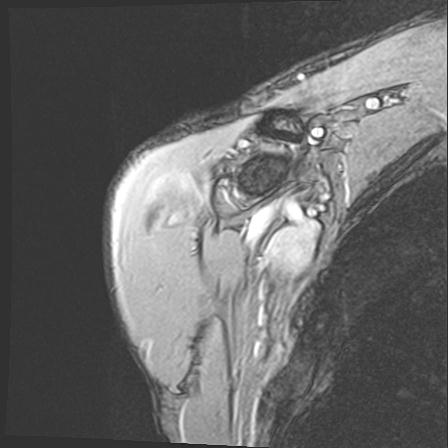

60058 3/9 11/4 右肩 2R+MRI 73歳男性 肩腱板損傷